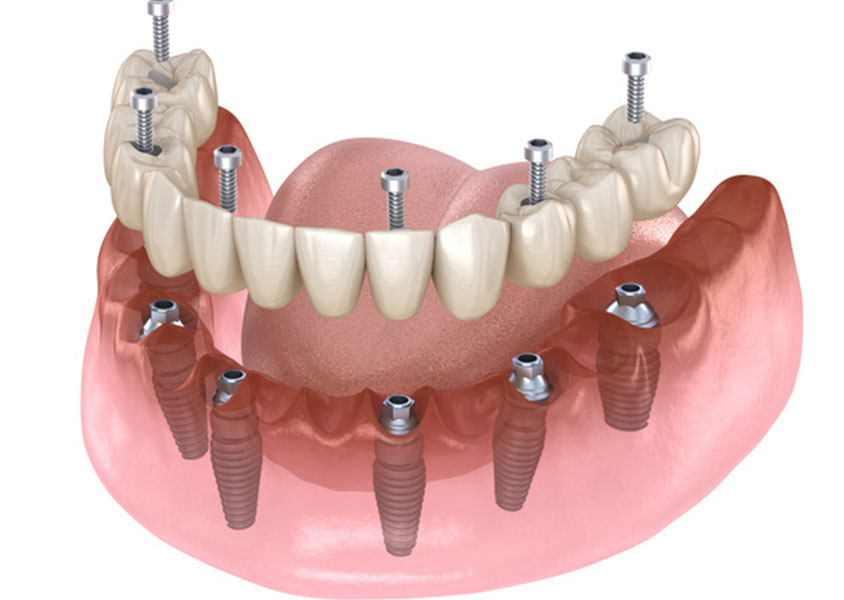

Zahnersatz

Müssen einer oder mehrere Zähne ersetzt werden, kümmern wir uns darum mit modernster Technik die beste Lösung für Sie zu finden. Gerne beraten wir Sie im Hinblick auf den für Sie in Frage kommenden Zahnersatz und erstellen einen unverbindlichen Kostenvoranschlag für die von Ihnen gewünschte Versorgung.